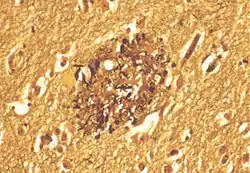

Obraz blaszki amyloidowej w mózgu chorego z chorobą Alzheimera

Blaszki amyloidowe, blaszki (płytki) starcze (ang. senile plaques) – zmiany strukturalne obserwowane w wielu chorobach neurodegeneracyjnych, m.in. w chorobie Alzheimera. Składają się z amyloidu, dystroficznych neurytów oraz komórek astrogleju i mikrogleju[1].

Blaszki neurytyczne najlepiej widoczne są w metodach impregnacyjnych, takich jak metoda Bodiana, Gallayasa albo Bielschowsky’ego. Słabo widać je w rutynowym barwieniu H-E.